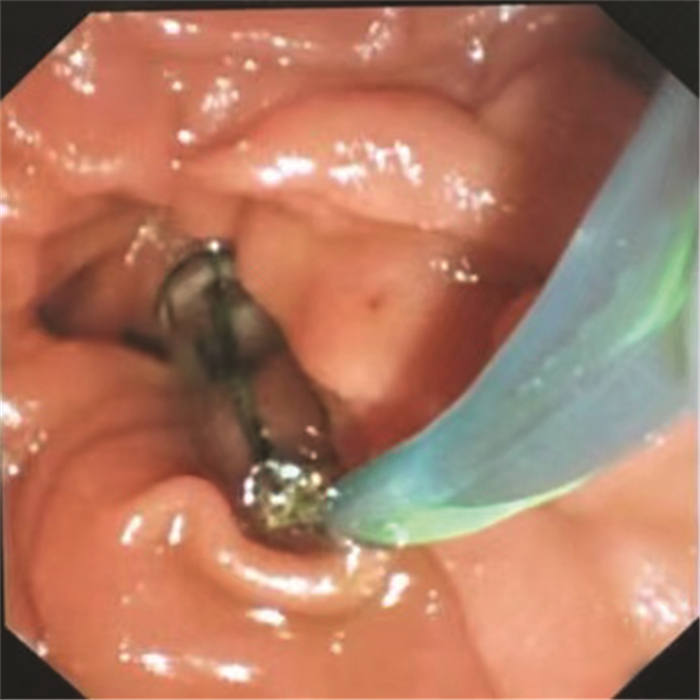

Chinese expert consensus on the endoscopic diagnosis and treatment of biliary fistula (2020, Beijing)

Chinese Society of Endoscopy, Chinese Medical Association, Endoscopic Physician Branch of Chinese Medical Doctor Association, Beijing Society of Digestive Endoscopy, Beijing Medical Association

2021, 37(4): 798-802. DOI: 10.3969/j.issn.1001-5256.2021.04.015

Abstract(1246) HTML (675) PDF (1978KB)(242)

Chinese expert consensus on the endoscopic diagnosis and treatment of pancreatic fistula (2020, Beijing)

2021, 37(4): 803-808. DOI: 10.3969/j.issn.1001-5256.2021.04.016

Abstract(1527) HTML (1001) PDF (1955KB)(238)

Abstract: